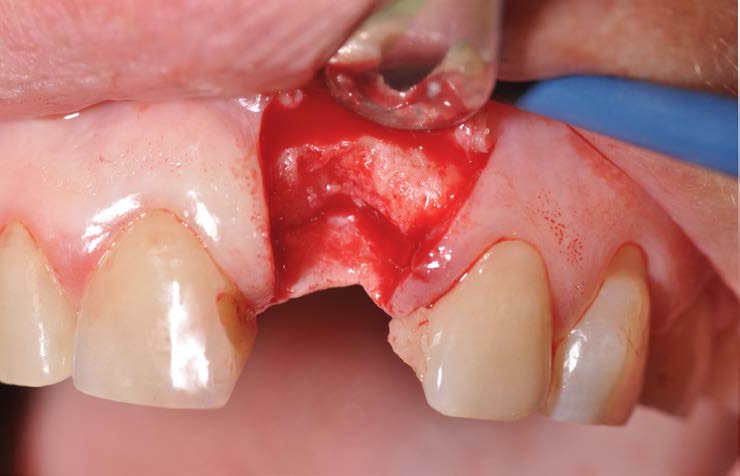

The radiographic examination (intraoral X-ray and Cone Beam Tc scan) shows vertical and horizontal bone defects due to alveolar remodeling following tooth extraction made many years earlier. It was decided to plan an implant insertion surgery and proceed with the insertion of a EV implant with a delayed loading with simultaneous regeneration of hard and soft tissues to obtain the correct volumes for aesthetic success.